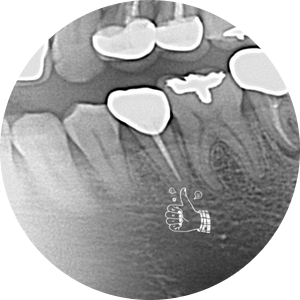

오른쪽 위 어금니 충치가 심해서 발치를 하자고 했었는데 미루시다가 이제는 너무 불편해서 안되겠다고 당분간 일을 쉬게 되어서 여유있게 다른 치료도 받고싶다고 하셨다.

원래 발치하기로 했던 치아는 더 썩어서 부러져 있어고 좌측 아래 작은 어금니도 그동안 충치가 많이 진행되어 신경치료가 필요한 상황이었다.

발치와 첫 신경치료는 수면마취로 진행하고 조심스럽게 말을 건내본다.

"신경치료는 한 번에 마무리하지 않고 중간에 신경관 내 감염 요소들을 소독하면서 증상을 봐야하는데 매번 수면 치료를 할 수는 없으니 간단한 진료는 비수면으로 진행해 보시죠. 매번 치과를 오실때마다 땀과 떨림... 극도의 긴장된 모습을 보이시는 환자분이라 나도 비수면으로 진료를 해보자는 말이 어려웠다..."